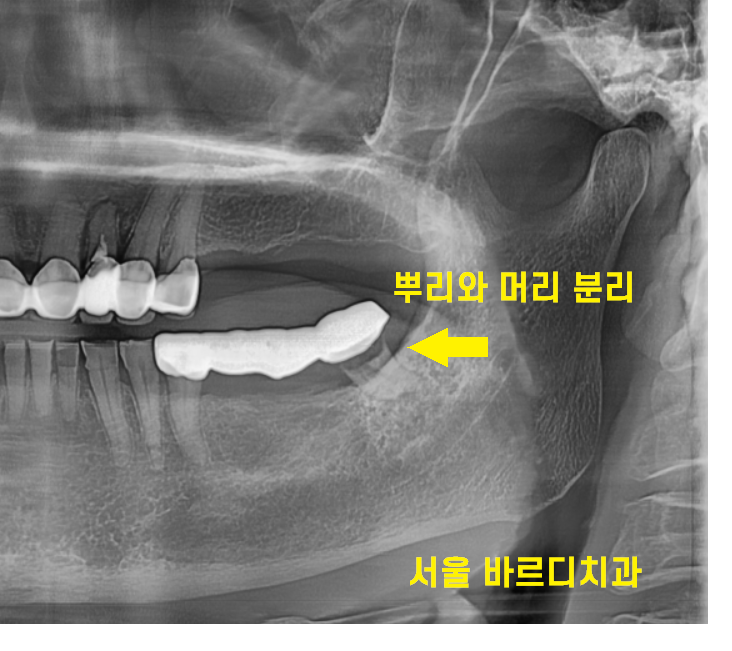

이런이런

전체 사진에서도 문제가 보이네요.

자세한 사진을 볼까요~?

2023.05.26

왼쪽 아래 보철물을 오래 쓰다보니

치아가 삭고 뿌리가 뿌러졌습니다.

머리와 뿌리가 분리된 상태